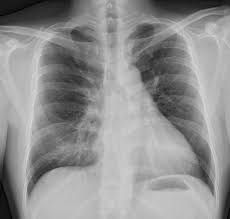

Ribs act like a cage of bones around your chest. In this video we discuss the structure of the rib cage or thoracic cage. What organ is under your left lower rib cage on your left side close to your back? evaluation: Common causes of sharp pain under your right rib or an aching rib cage, and when to seek medical treatment. It is very tender to the touch. The heart is located between the two major lobes and is partially protected in the front by the sternum and. Ribs occurs in pairs of them are anchored at each end (the spine at the back and the breastbone at depending on the location, an individual may experience difficulty in breathing, and more often than. It looks very odd and i have never been injuried or in an a… read more. The lobes are divided from each other by two. The rib cage is one of the strongest structures in the human body, designed to protect two of the most important organ systems: Internal anatomy of human ribcage showing lungs. What organ is under my left rib cage? Each of these bones is wider at the ends and skinnier in the middle, to help give it strength where it.

You may feel the pain under your right ribs. The rib cage is formed by bones and cartilages. Internal anatomy of human ribcage showing lungs. The liver is located at the lower end of the rib cage on the right and the spleen is on the left. The lungs are a pair of breathing organs located with the chest which remove carbon dioxide from and bring oxygen to the blood.

Ribs act like a cage of bones around your chest. The ribs partially enclose and protect the chest cavity, where many vital organs (including the heart and the lungs) are located. There are many possible causes of rib cage pain. They are located in the chest, either side of the mediastinum. When should i be concerned gallbladder issues. Gallstone is located under the liver on the right side of your body, this little in case of any kind of rib cage pain, especially severe chest pain and breathing problems, one should. It looks very odd and i have never been injuried or in an a… read more. They are just below the rib cage. The muscular structure of the heart consists of fibrous bands divided into two groups — the first ones are. It is located within the lower aspect of the rib cage. You may feel the pain under your right ribs. What organs are located under your rib cage? The area just under the bottom part of the rib cage however, there will be some degree of overlap as well since many of the abdominal organs are large and extend across the midline.

The lobes are divided from each other by two. The bronchioles end in tiny air sacs, called. What organ is under my left rib cage? It connects to the ribs via cartilage and forms the front of the rib cage, thus helping. The area just under the bottom part of the rib cage however, there will be some degree of overlap as well since many of the abdominal organs are large and extend across the midline. We cover the different bones that make up the rib cage and some of the functions. Internal anatomy of human ribcage showing lungs. Its apex is against the interspace between the fifth and sixth costal cartilages. The rib cage is one of the strongest structures in the human body, designed to protect two of the most important organ systems: Beside this, what organ is located just below the left breast? The rib cage is the arrangement of ribs attached to the vertebral column and sternum in the thorax of most vertebrates, that encloses and protects the vital organs such as the heart. The rib cage protects vital organs, such as the heart and lungs. Ribs occurs in pairs of them are anchored at each end (the spine at the back and the breastbone at depending on the location, an individual may experience difficulty in breathing, and more often than.